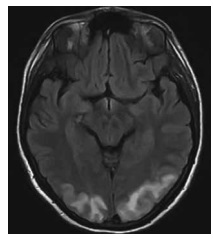

Uma mulher de 54 anos de idade, diabética, hipertensa e dislipidêmica, em uso irregular de medicações, compareceu ao pronto-socorro com cefaleia intensa, vômitos, náusea, turvação visual e escotomas. O acompanhante relatou que o quadro evoluiu paulatinamente durante os últimos dias, com piora importante no dia atual. Na admissão, foram notados os seguintes sinais vitais: FC 117 bpm; PA 210 x 145 mmHg; FR 21 irpm; e dextro 120.

Enunciado 4079866-1

Ainda com base na situação hipotética apresentada, e na imagem da ressonância magnética de crânio acima, assinale a alternativa correta.

Considerando essa situação hipotética, assinale a alternativa correta.